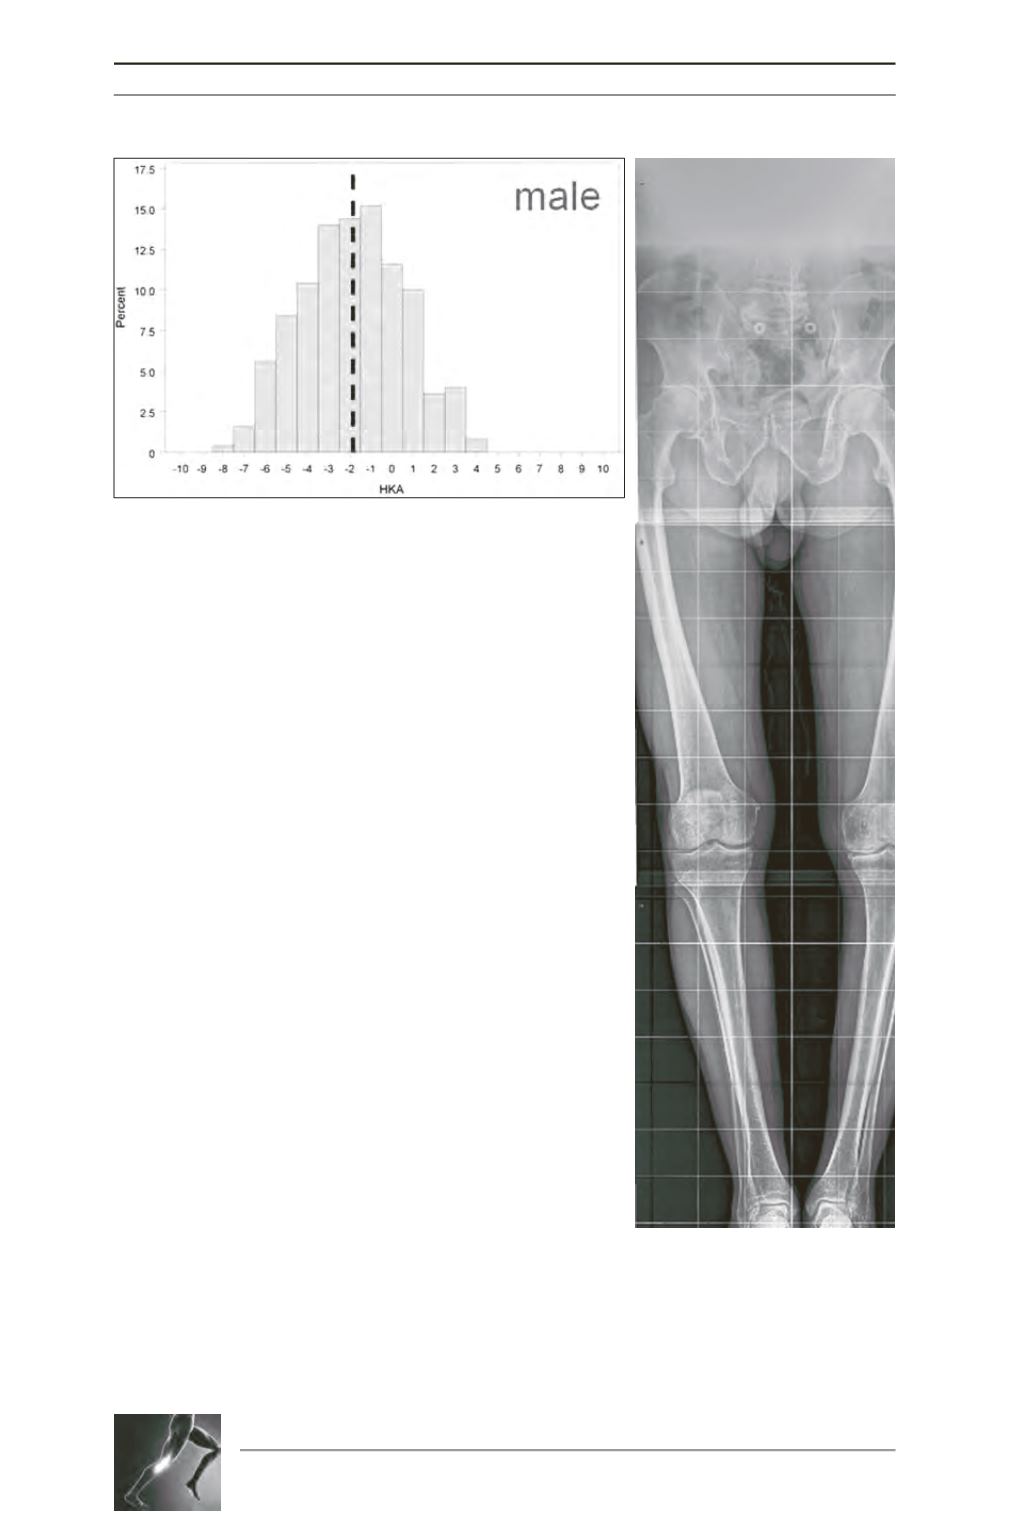

Fig. 1: Histogram depicting the large variability in natural alignment

in healthy male individuals, which contradicts the general belief that

normal alignment is zero. In fact large variability exists between

individuals, and the average alignment in males is around 2° varus.

Fig. 2: Typical constitututional

varus knee with medial OA (left)

requiring knee arthroplasty. The

typical characteristics are clearly

shown; varus OA of the knee, varus

hip neck-shaft angle, varus femoral

bowing, and varus of the

unaffected leg.